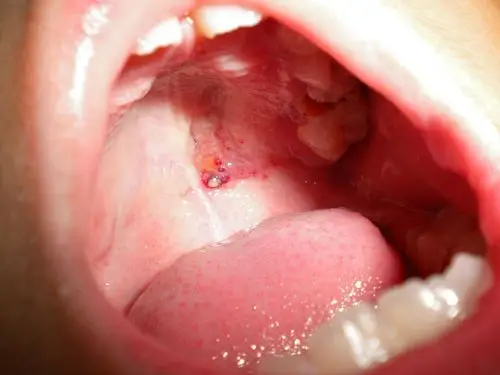

口腔上颚貌似上火发炎,感觉不像一般溃疡

家里的亲戚上颚长了个肿物,不痛不痒,不红,想请问一下是什么东西

口腔上颚长肿块,有些硬的,一个消了又长一个,怎么才能好

口腔硬颚肿块很怕